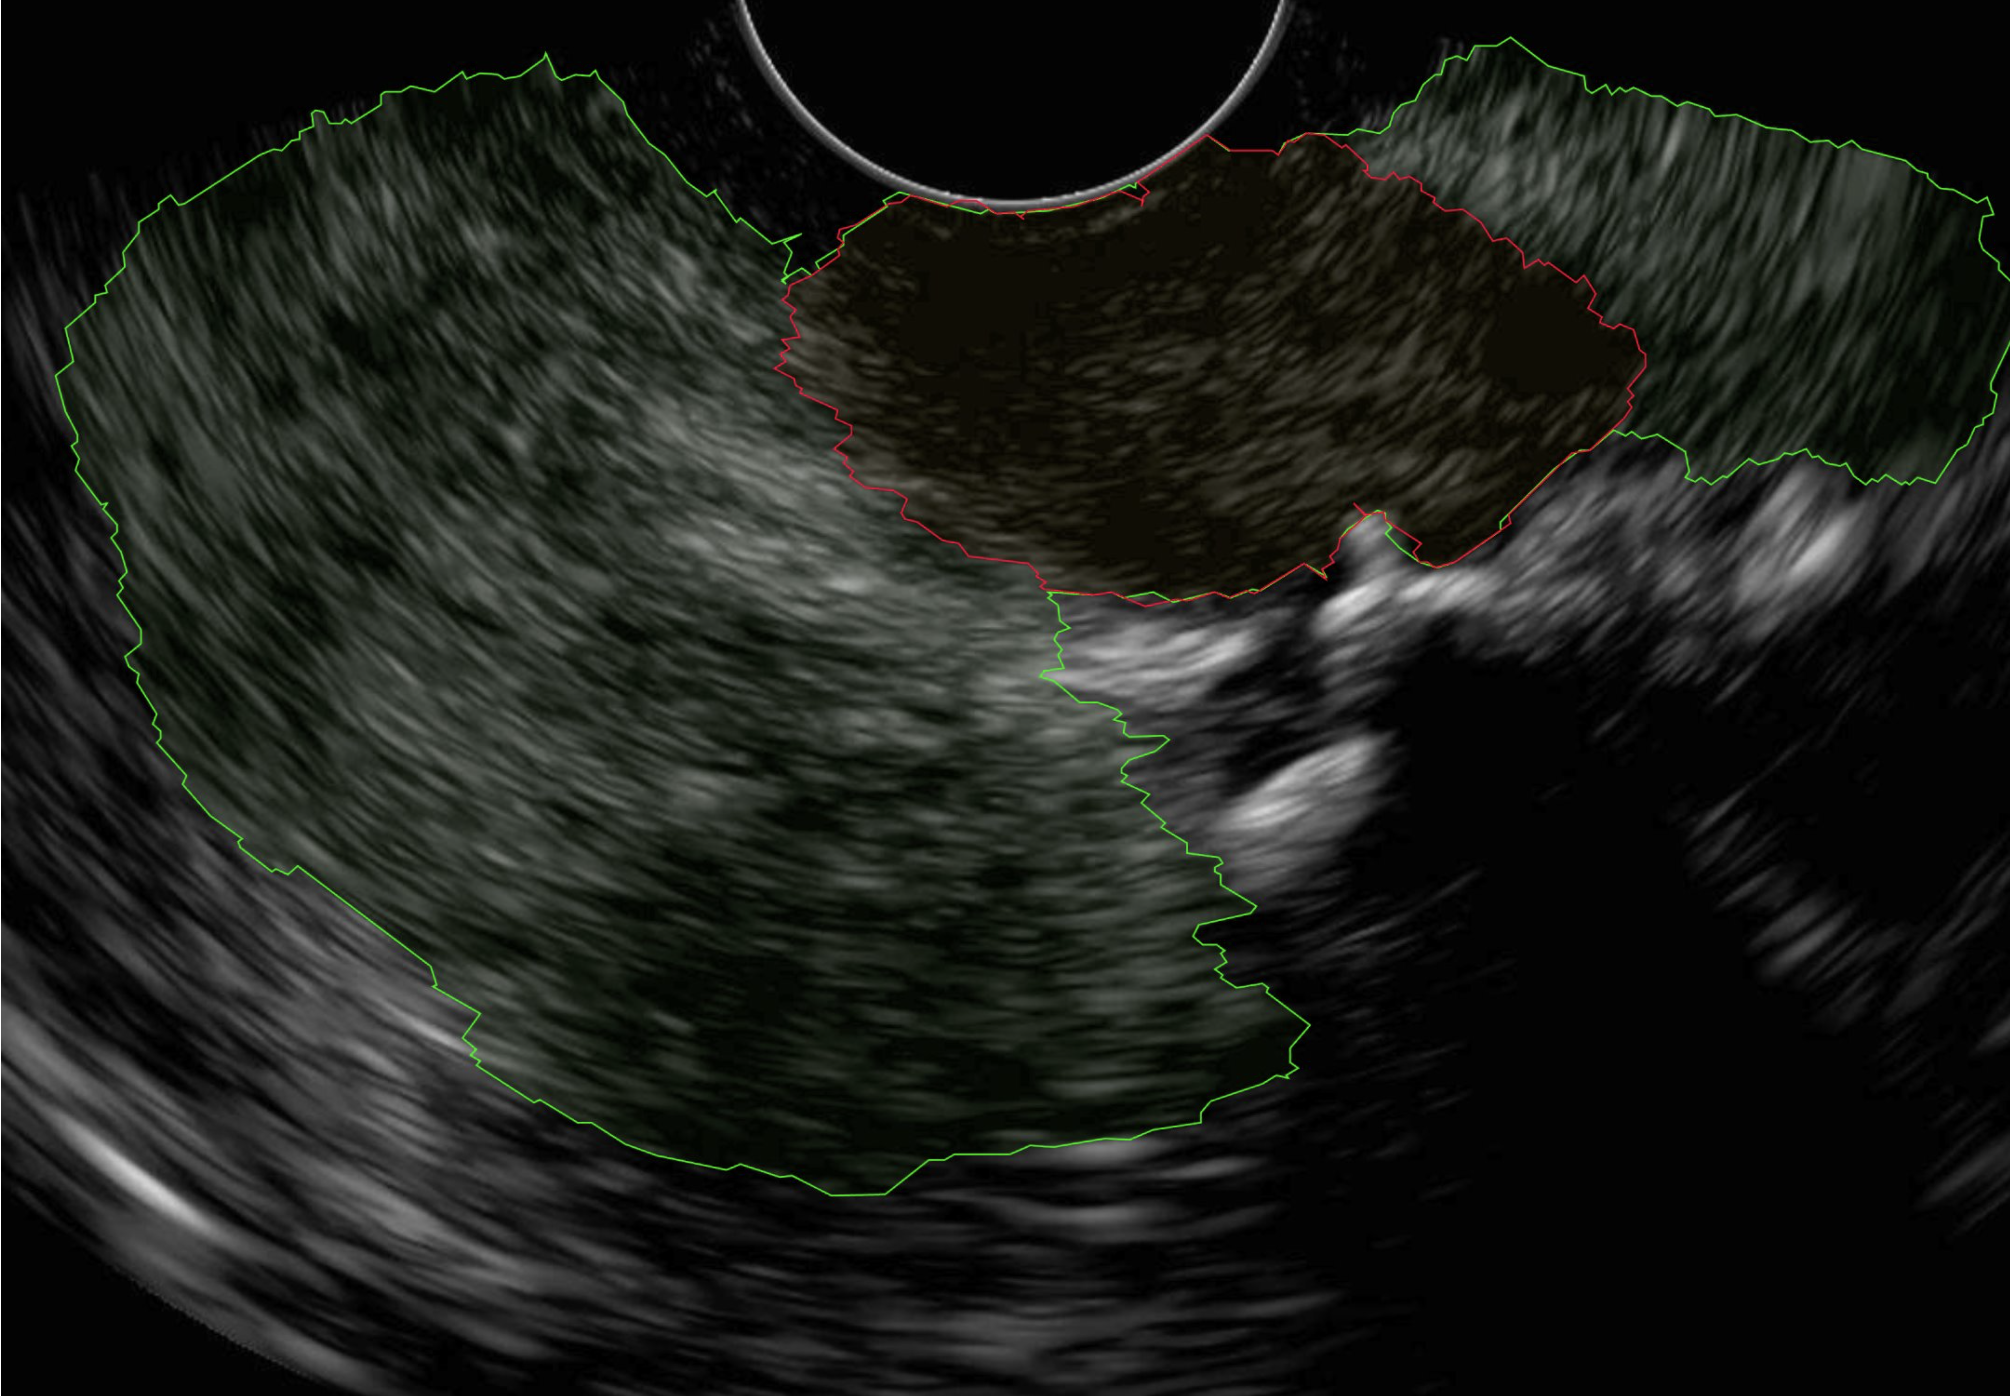

EUS-ML

Pancreatic cancer detection using Endoscopic Ultrasound (EUS).

Developed tools for pancreatic cancer detection using Endoscopic Ultrasound (EUS). The project involved Segmentation (finding the pancreas and tumor) and Classification (determining if a patient has cancer). The team utilized a dataset comprising 400+ annotated patient videos.

Cancer detection

94.12% sensitivity, 86.30% specificity, and 98.44% NPV (Negative Predictive Value).

Segmentation

70% DICE score for pancreas segmentation.

Real-time performance

EUSML-Inference App runs at ~21.28 FPS for real-time use during procedures.